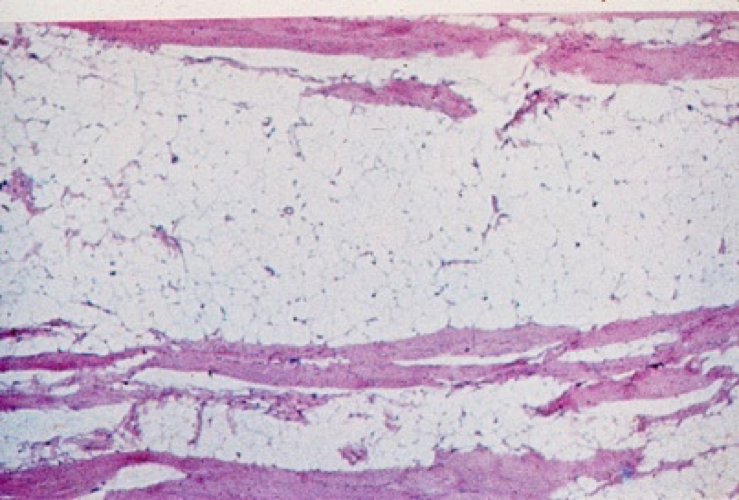

What is this characteristic of?

Demyelinating neuropathy -